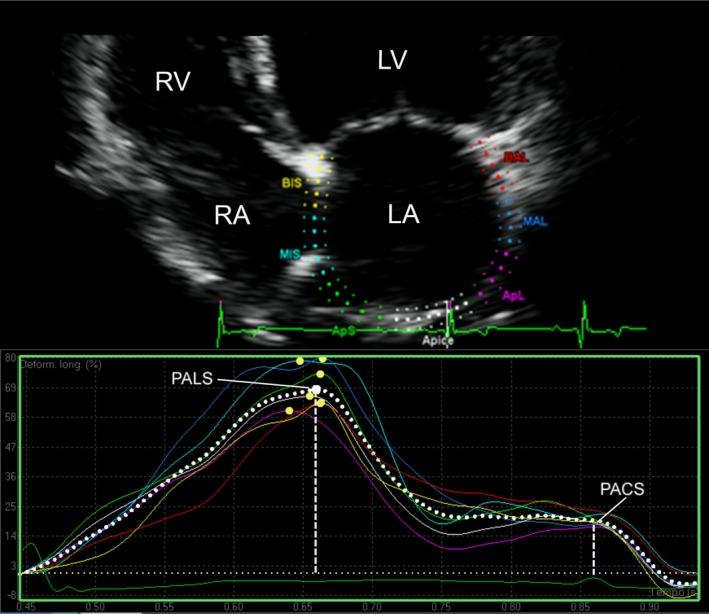

Variability study showed good reproducibility for all the tested variables (coefficient of variation <16%). Left atrial areas, fractional area change, peak atrial longitudinal strain (PALS), peak atrial contraction strain, and contraction strain index (CSI) differed significantly between groups B2 and C + D and all the other groups (overall P < .001), whereas only PALS differed between groups B1 and A (P = .01). Left atrial areas increased with progression of the disease, whereas LA functional parameters decreased. Only CSI increased nonsignificantly from group A to group B1 and then progressively decreased. Thirty-one significant correlations (P < .001, r > .3) were found between conventional left heart echocardiographic variables and LA areas and strain variables.

变异性研究表明,所有测试变量均具有良好的重复性(变异系数<16%)。B2组与C + D组以及所有其他组之间,左心房面积、面积变化分数、心房纵向峰值应变(PALS)、心房收缩峰值应变和收缩应变指数(CSI)存在显著差异(总体P <.001),而B1组与A组之间仅PALS存在差异(P =.01)。左心房面积随疾病进展而增加,而LA功能参数下降。仅CSI从A组到B1组无显著增加,然后逐渐下降。在传统左心超声心动图变量与LA面积和应变变量之间发现了31个显著相关性(P <.001,r>.3)。